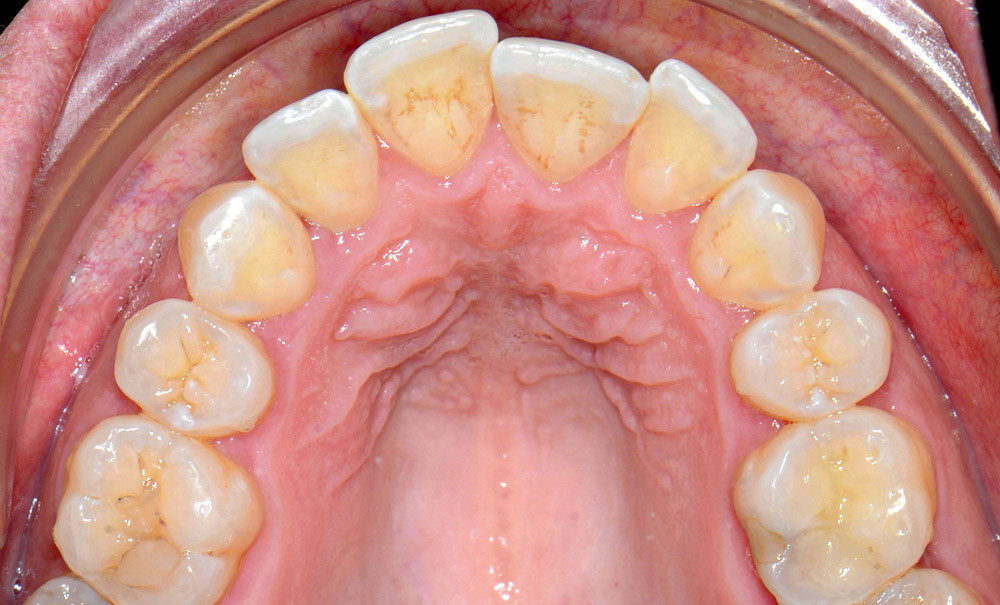

C’est précisément le cas de cette patiente de 33 ans qui présente une classe II squelettique par rétrognathie mandibulaire sur un schéma vertical hyperdivergent associée à une classe II/1 dentaire avec DDA par excès et biproalvéolie. Son profil est convexe, cis-frontal et, sur le plan fonctionnel, on peut observer une dysfonction linguale et une incompétence labiale au repos. Il en résulte une contracture des muscles de la sphère péri-orale lèvres jointes. La formule dentaire n’est pas complète puisque les quatre deuxièmes prémolaires ont été extraites lors d’un premier traitement orthodontique et qu’il y a également agénésie des troisièmes molaires 18 et 38 (fig 1 à 11).

Au regard de ces éléments, la décision thérapeutique choisie intègre une prise en charge orthodontique associée à une chirurgie orthognathique d’avancement mandibulaire et à une mentoplastie. L’étape initiale du traitement orthodontique consiste en la levée des compensations dentaires qui se traduit par la correction de la proalvéolie mandi– bulaire dans le but de pouvoir corriger la classe II squelettique et dentaire par avancement chirur- gical de la mandibule. Pour cela, des mini-vis d’ancrage sont positionnées distalement aux secteurs 3 et 4, enfouies à la base des branches mandibulaires avec des chaînettes métalliques émergentes dans la cavité buccale. L’objectif est d’assurer le repositionnement incisif mandibulaire grâce à des modules élastiques.